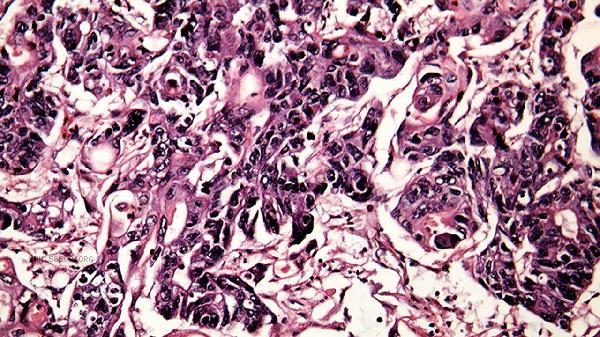

Chronic myelomonocytic leukemia, myelodysplastic syndrome, etc. can lead to clonal proliferation of monocytes. A blood smear shows immature monocytes, while bone marrow biopsy can detect pathological hematopoiesis, which requires specialized evaluation in hematology.